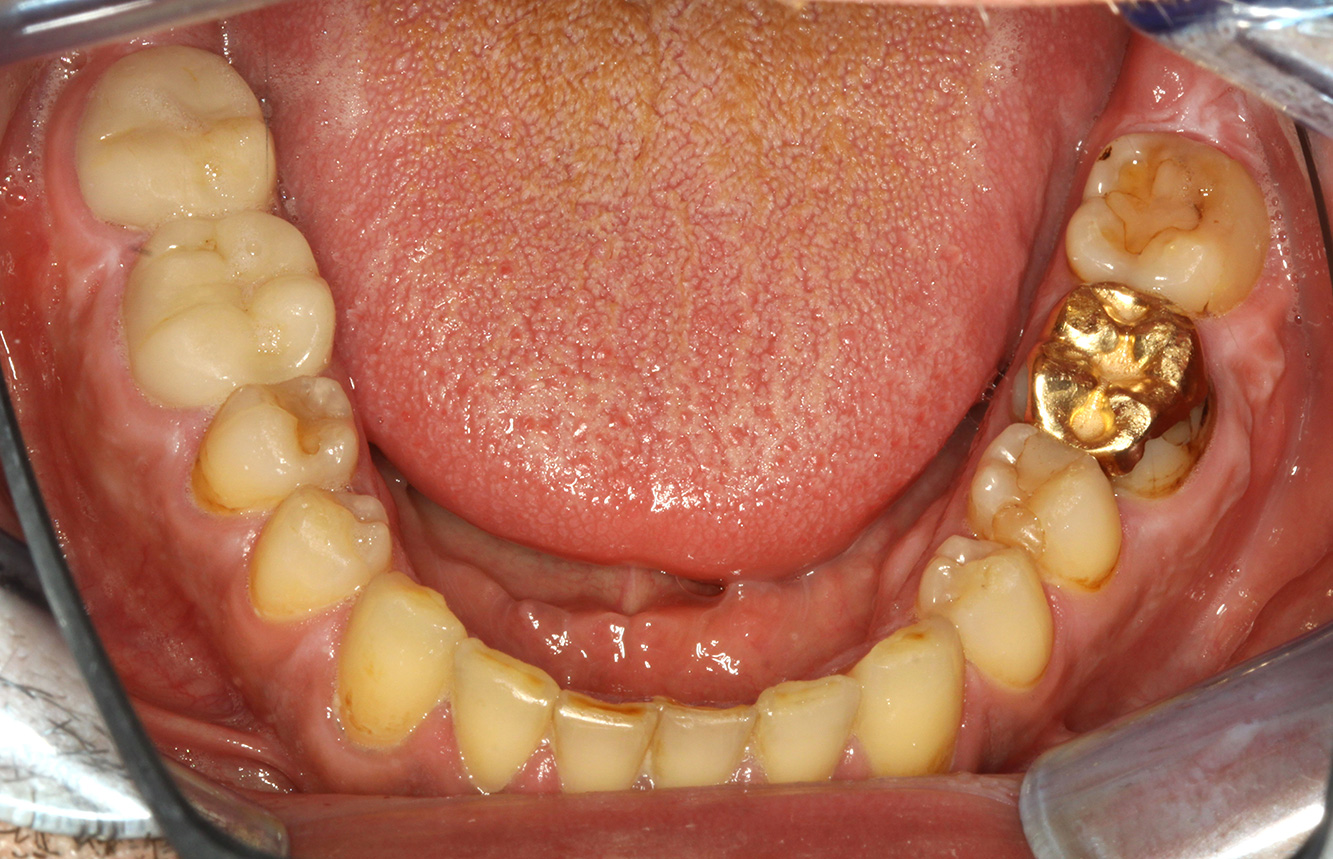

Fotos: © Dr G. Schmalz y Dr D. Ziebolz MSc

El paciente tiene 39 años con valvuloplastia frente a una insuficiencia valvular y endocarditis. Toma regularmente ASS 100 (ácido acetil salicílico) como anticoagulante. En el ámbito del estilo de vida, la alimentación se identifica como promotora de caries, ya que suele consumir alimentos azucarados y seis o siete comidas al día. La salud oral del paciente muestra un riesgo medio de caries con lesiones activas. El riesgo de periodontitis es bajo, presenta gingivitis. Se hacen las siguientes recomendaciones para el tratamiento profiláctico.